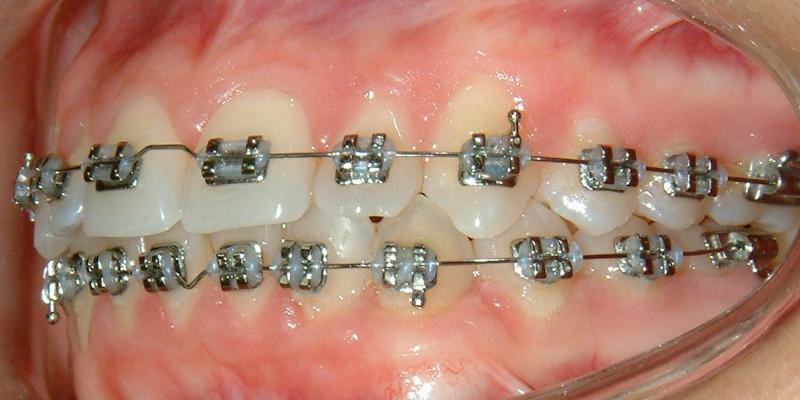

Without surgical exposure and forced eruption, there was practically very little progress with natural eruption of the upper left canine for nearly 2 years (not shown). With the surgical exposure (laser -> no bleeding) and forced eruption, the progress can be seen almost immediately - within a month (Figs. 3-5), and a complete success in four months (Fig. 6).

Fig. 5 One month after surgery: good eruption of canine

© Copyright 2007-2014, Vu Orthodontics. All rights reserved.